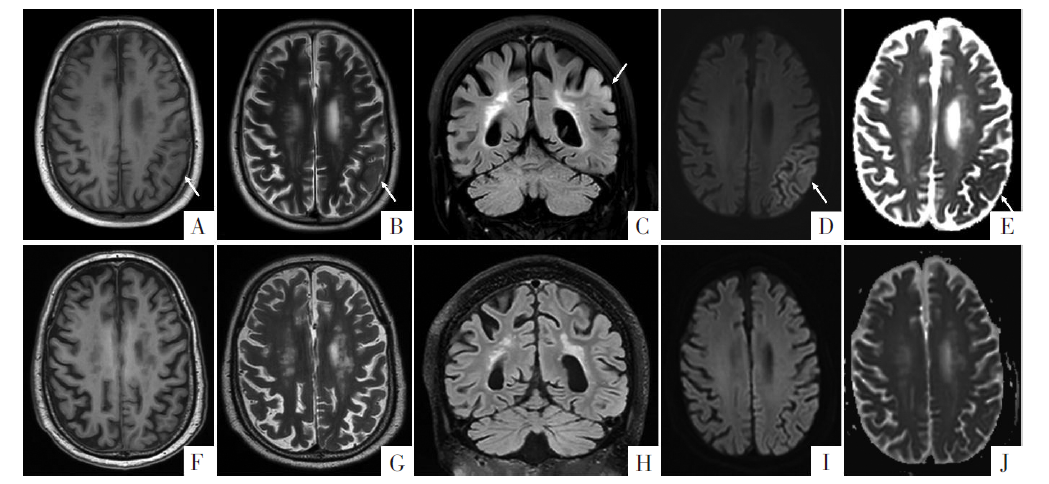

图1

头颅MRI影像。A-E图分别为T

1

WI、T

2

WI、FLAIR、 DWI和ADC图。F-J图为治疗后影像,异常信号消失。